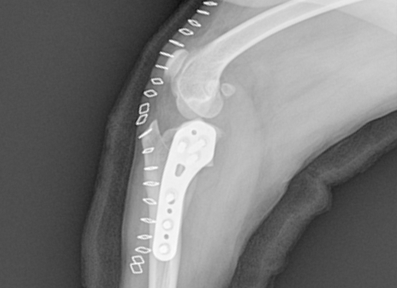

전십자인대 질환 (Cranial Cruciate Ligament Disease)

전십자인대 파열은 반려견에서 가장 흔한 무릎 관절 질환으로, 심할 경우 보행이 어렵고 심한 통증을 유발합니다. 본원은 뼈 구조, 체중, 활동 수준 등을 고려하여 TPLO, CTWO 등 다양한 수술 방법 중 가장 적합한 수술법을 선택해 맞춤 치료를 진행합니다. X-ray와 CT 영상을 통해 인대 손상 정도와 관절 상태를 정밀하게 진단하고, 수술 전 시뮬레이션을 통해 오차를 최소화합니다. 수술 후에는 통증 관리와 재활 운동, 근력 강화 프로그램을 통해 기능 회복을 돕고 재발을 예방합니다.